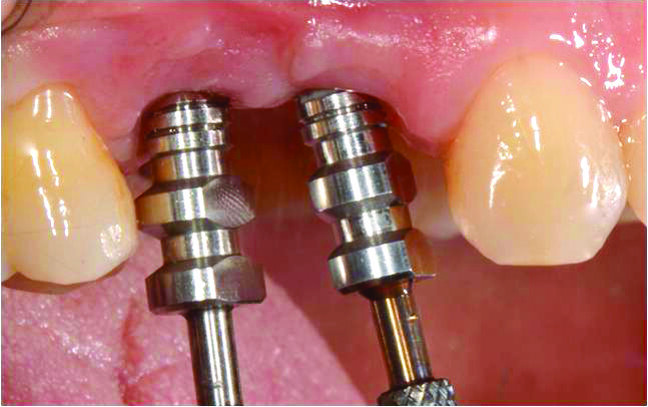

In questo caso si mostra come un incremento stabile dei tessuti molli, eseguito contestualmente all’inserimento di impianti, possa essere intrapreso senza far ricorso a prelievi di tessuto dal palato, eliminandone i rischi correlati, ovvero sanguinamento eccessivo, infezione tissutale post-operatoria, edema e compromissione della guarigione del sito donatore e morbilità per la presenza di due diversi siti chirurgici in sedi distanti (sella edentula e palato)5. Il piano di trattamento prevede una procedura chirurgico-protesica con utilizzo di impianti postestrattivi precoci a carico immediato in sede 14 e 15, abbinati a innesto di connettivo vestibolare (Fig. 4). La scelta ricade su due impianti ICE (Alpha-Bio Tec, Israele) di diametro 3,75 x 11,5 in sede 14 e 4,2 x 11,5 in sede 15. La consegna del manufatto protesico definitivo avviene a 4 mesi dall’intervento chirurgico.

La preparazione dei siti implantari avviene mediante frese DNT2 (Alpha-Bio Tec, Israele) che dispongono di tacche di profondità evidenziate in contrasto cromatico e codici-colore per una migliore identificazione della profondità dell’osteotomia. Tali frese presentano tre scanalature e un’innovativa conformazione delle lame per praticare l’ostoetomia con precisione e massima stabilità nel taglio6. L’innovativo design delle frese DNT2 consente, inoltre, una ridotta produzione di calore durante la perforazione e l’alesatura del sito implantare (Fig. 5). La procedura osteotomica viene eseguita con tecnica flapless in modo da ridurre al minimo il riassorbimento vestibolare dell’osso crestale7 e la sintomatologia nel post-operatorio.

Fig. 5_Il pin di profondità guida la preparazione del sito del 14 con una leggera inclinazione distale della fresa per evitare di impattare la radice del 13.